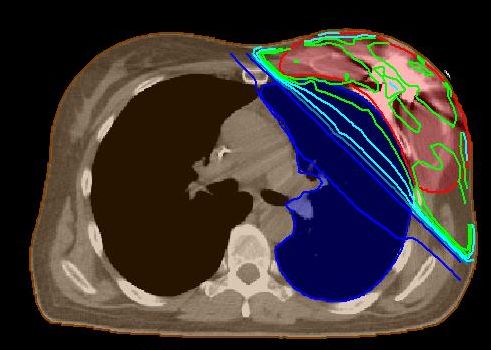

| Dosimetrie | Messungen mit einer p-Type - Diode ergaben eine Abschwächung der Dosis bis 30% (1). | Bei tangential opponierenden Feldern beträgt die Unterdosierung ca. 10%. | Das Planungssystem konnte die Dosis nicht exakt berechnen. | |